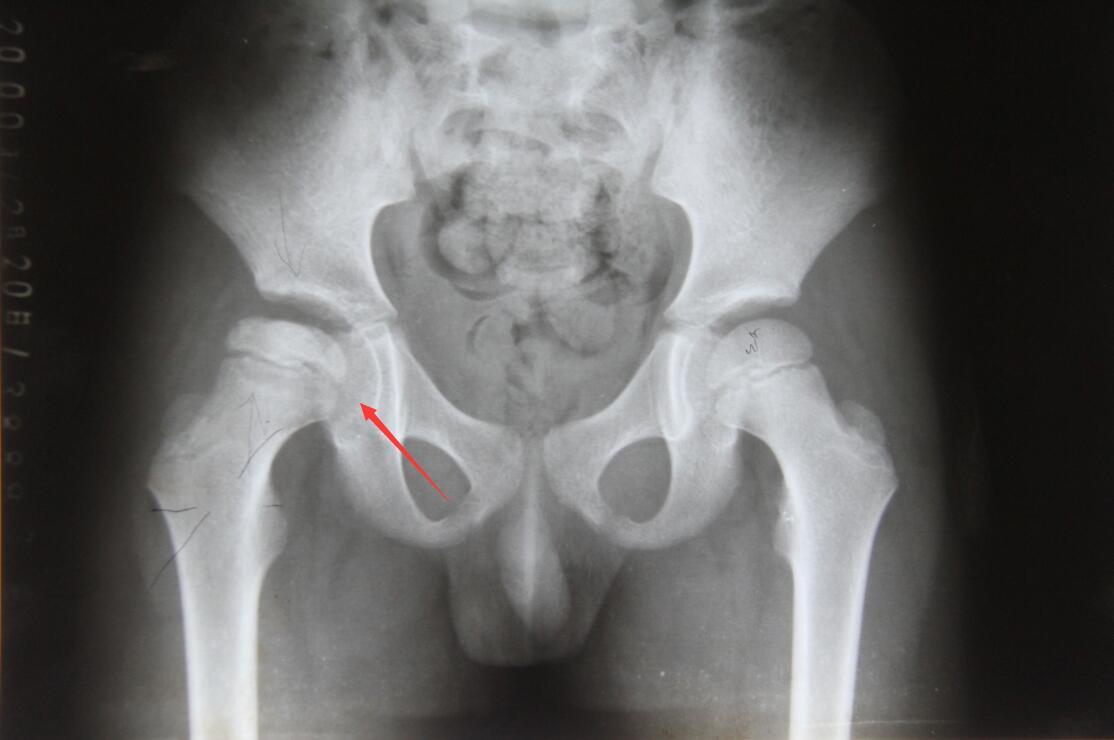

继发甲状旁腺机能亢进症的影像学变化包括:内骨、骨皮质和骨膜的骨吸收、指末趾骨腐蚀、囊肿形成和骨硬化。在这些变化中,骨膜吸收是最常见的影像学改变,主要发生在指骨,还有骨表面、锁骨远端和肋骨,尺骨,胫骨,下颌表面。

骨质硬化的影像学变化导致骨密度增加,而干骺端和软骨病变的诊断则依赖于椎体、骨盆、肋骨、锁骨和各种长骨。仅有的影像学检查显示骨束松动和假骨折,这通常降低了骨密度,但不足以诊断骨软化。放射学检查发现骨密度降低,常用于患有长期肾衰竭的病人。